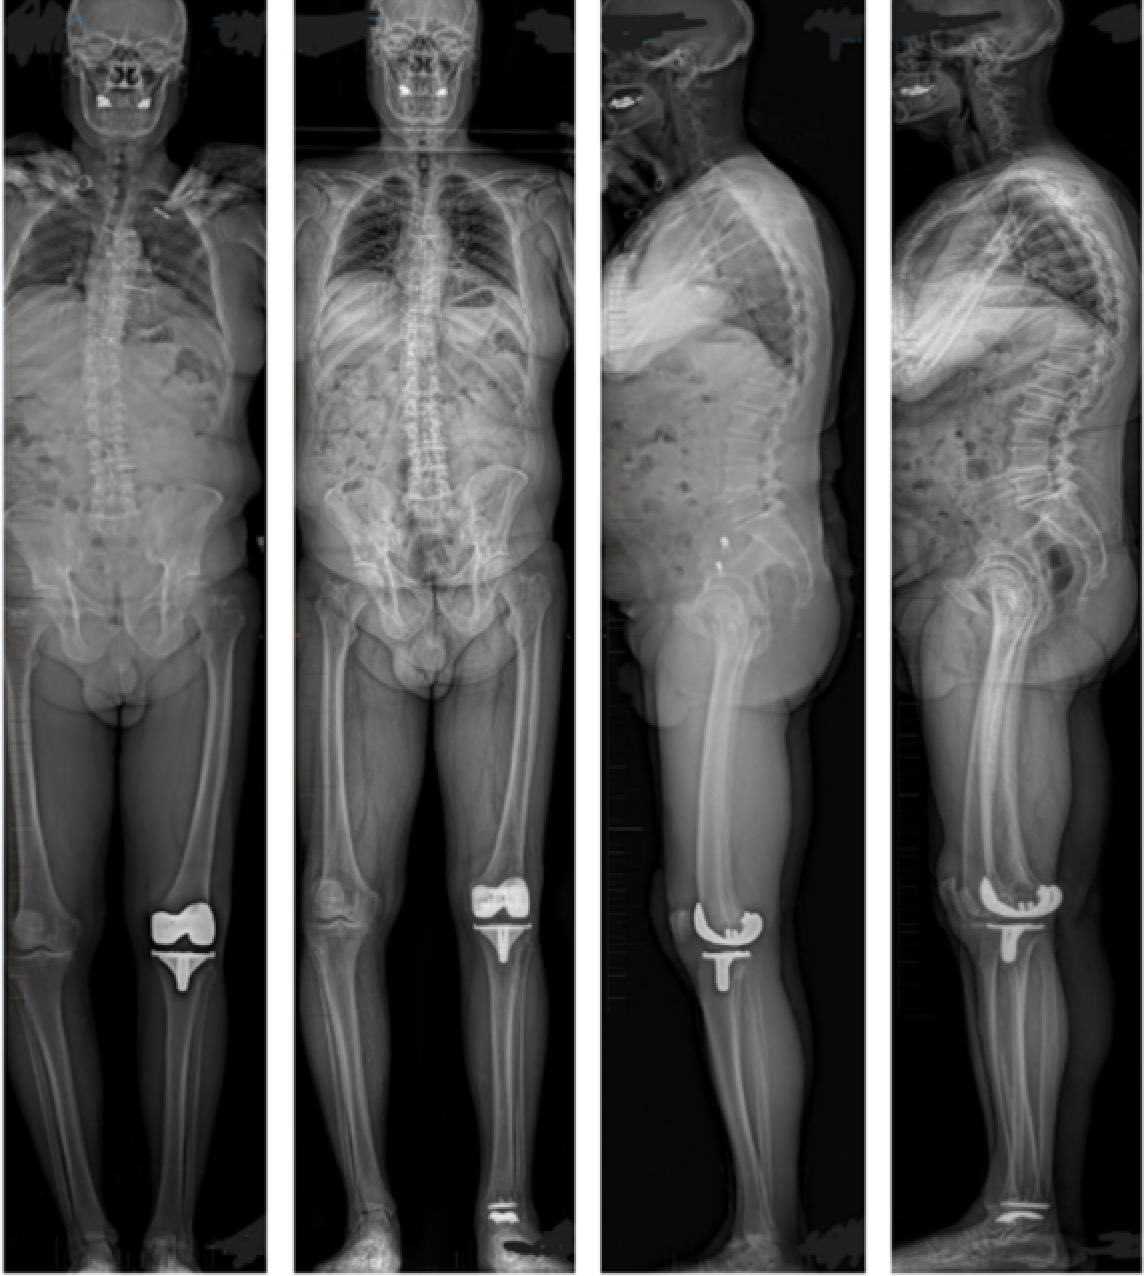

EOSedge is a precise, low dose imaging system that delivers full body images covering the full set of musculoskeletal and orthopaedic exams.

• Full body images in standing position

Image shows EOS original (left) compared to EOSedge (right).

The EOSedge provides high-resolution images with excellent contrast and minimal noise compared to older systems, aiding in accurate diagnosis and treatment planning.